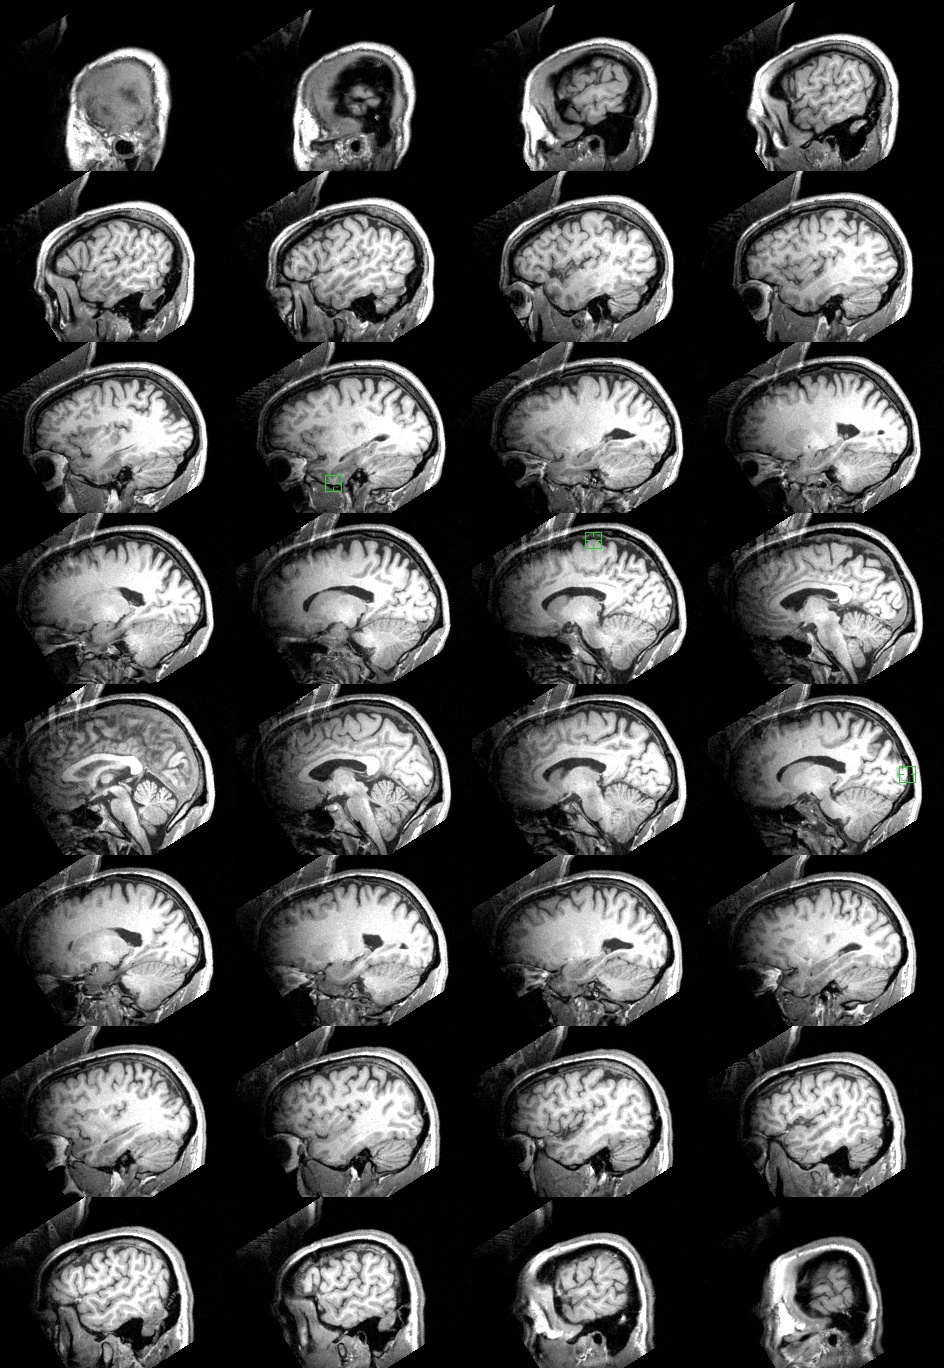

Sagittal slices: These images progress from left in the upper left to right in the lower right. |